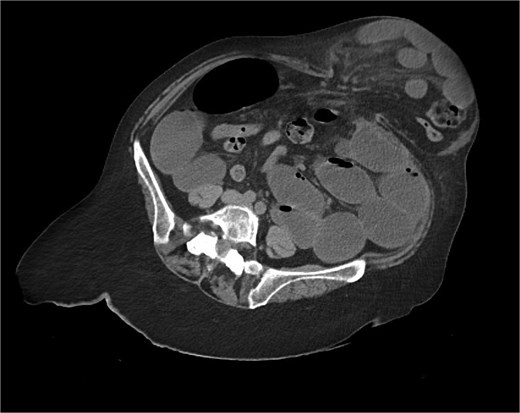

Immediate action involved removing fluid from the gastric band and inserting a nasogastric tube, which was slightly difficult. Only 200 ml of gastric content was drained, and no air was present (indicating that it was not in the stomach). Given the possibility of anatomical pathology or obstruction at the gastroesophageal junction (GEJ), we avoided excessive force when inserting the tube to prevent iatrogenic esophageal perforation. A computed tomography (CT) scan with liquid-soluble contrast media showed that the contrast did not pass beyond the band. The scan also revealed massive gastric dilatation, as well as dilation of the esophagus proximal to the band (Figs 2–4).

CT axial view—contrast media in distal esophagus did not pass to the stomach.

The CT also showed a large ventral hernia in the anterior abdominal wall on the left side, with several entrances and exits for intestinal loops within the hernia. The proximal loops appeared dilated up to 5 cm, with fat stranding and slight fluid between the loops, as well as mild prominence of the mesenteric blood vessels. Distal loops were collapsed, raising suspicion of high-grade obstruction with ischemic bowel involvement (Fig. 5).

CT axial view—obstructed ventral hernia with proximal small bowel loop dilatation.